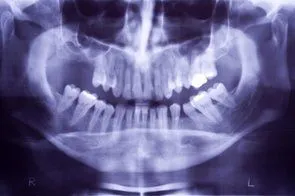

When you lose teeth, and do not replace them, the jawbone deteriorates where the tooth socket once was. This makes it difficult, and in some instances impossible to get dental implants or dentures later on. You may have not had the financial means at the time of the extraction for restorative surgery, but you may have the money now. The good news is that we can perform a process called ridge augmentation to restore the bone structure that is needed for restorative procedures such as dental implants. The process involves lifting the gum from the ridge to expose the defected area of the bone. Then the dentist uses a bone like substance to fill the defected areas. The ridge augmentation greatly improves the appearance of the mouth and increases the chances for success with the implants. With ridge augmentation, your implants will last for years.